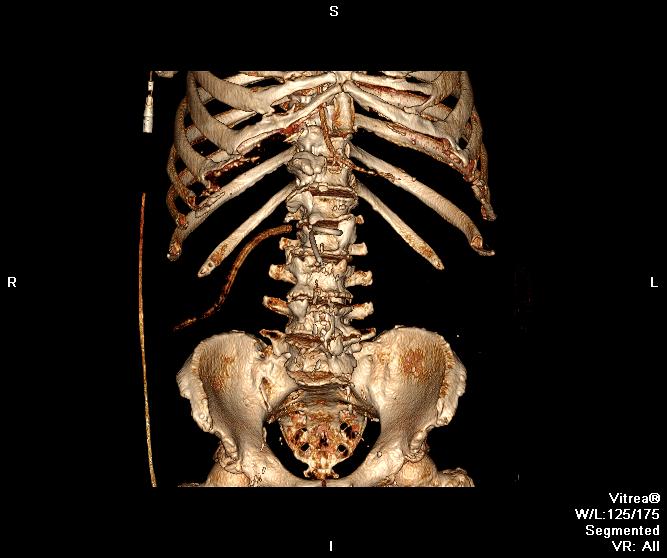

Пациент оперирован по поводу аденоКа толстого кишечника, гемиколэктомия. Онкопоиск, поиск вторичного поражения.

В воротах печени беда, но не об этом сейчас. Прицельно смотрим контраст.

Во втором случае наблюдается гиподенсный участок в печени.

дифференцируем между метастазом и холангиокарциномой